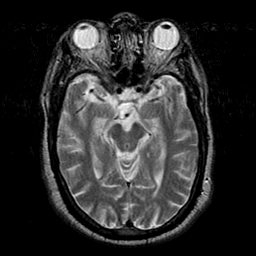

Subacute Stroke overlay -- Slice #9

[Home][Help][Clinical] Slice 9